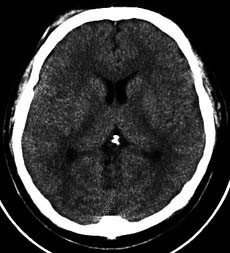

頭部CT

X線を使用する撮影ですが、細いX線ビームを回転しながら出してそれをコンピュータ画像処理したものです。

スライス番号は、すぐ下のCT画像に対応しています。上段の図をクリックすると下段のCT画像が拡大して見られます。